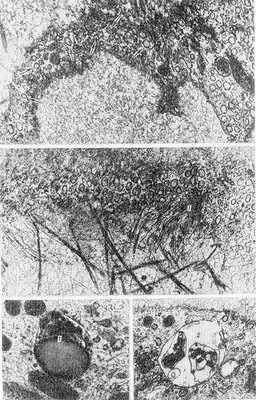

Рис. 5. Схематическое изображение строения стенки лимфатического капилляра с элементами окружающей соединительной ткани; 1 — эндотелиоцит; 2 — просвет лимфатического капилляра; 3 — коллагеновые протофибриллы соединительной ткани; 4—«якорные» филаменты; 5 — соединительная ткань.

Рис. 6. Электронограмма элементов стенки лимфатических капилляров и окружающей их соединительной ткани: а — эндотелиоцит (стрелками указаны микропиноцитозные везикулы); х 20 000; б — «якорные» филаменты (1), фиксирующие эндотелиоцит (2) к окружающим его коллагеновым протофибриллам (3); х 50 000; в и г — цитоплазма эндотелиоцитов (1 — лизосома, 2 — остаточное тельце); X 60 000.

Лимфатические капилляры

Лимфатические капилляры (рис. 5 и 6) представляют собой систему замкнутых с одного конца эндотелиальных трубок, которые выполняют дренажную функцию — участвуют во всасывании из тканей фильтрата плазмы и крови (жидкости с растворенными в ней коллоидами и кристаллоидами), некоторых форменных элементов крови (лимфоцитов, эритроцитов), участвуют также в фагоцитозе (захват инородных частиц, бактерий). Лимф. К. отводят лимфу через систему интра- и экстраорганных лимф, сосудов в главные лимфатические коллекторы — грудной проток и правый лимфатический проток (см. Лимфатическая система). Лимф. К. пронизывают ткани всех органов, за исключением головного и спинного мозга, селезенки, хрящей, плаценты, а также хрусталика и склеры глазного яблока. Диаметр их просвета достигает 20—26 мкм, а стенка, в отличие от кровеносных К., представлена лишь резко уплощенными эндотелиоцитами (рис. 5). Последние примерно в 4 раза крупнее, чем эндотелиоциты кровеносных К. В клетках эндотелия, кроме обычных органелл и микропиноцитозных везикул, встречаются лизосомы и остаточные тельца — внутриклеточные структуры, возникающие в процессе фагоцитоза, что объясняется участием лимф. К. в фагоцитозе. Другая особенность лимф. К. заключается в наличии «якорных», или «стройных», филаментов (рис. 5 и 6), осуществляющих фиксацию их эндотелия к окружающим К. коллагеновым протофибриллам. В связи с участием в процессах всасывания межэндотелиальные контакты в их стенке имеют различное строение. В период интенсивной резорбции ширина межэндотелиальных щелей увеличивается до 1 мкм.